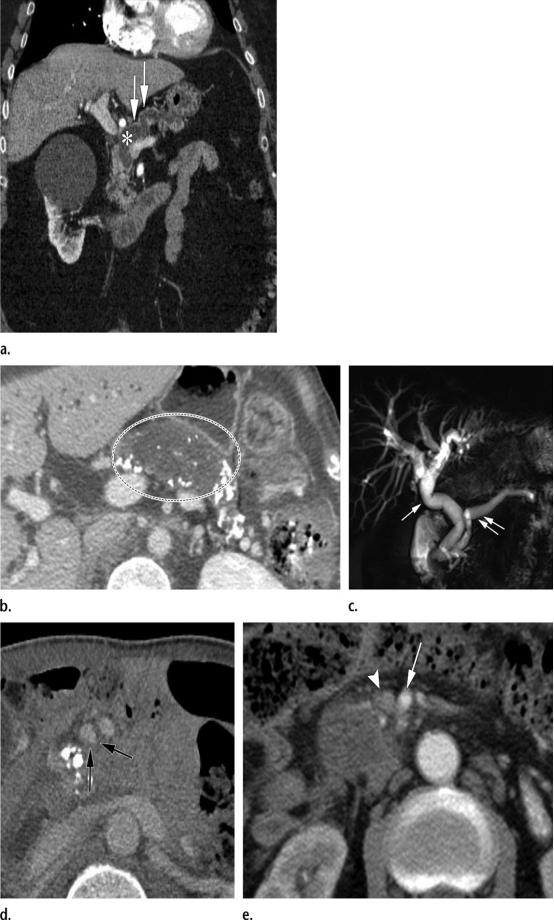

倾向于炎性病变(或肿块形成型胰腺炎),而非胰腺恶性肿物的影像学表现。

(a图)冠状位T2WI磁共振示胰头区域不均匀的肿物样病变(黑色长箭头),主胰管近端管径缩小,但可见横穿此肿物(白色长箭头)。

(b图)磁共振胆胰管成像,清晰显示肿物样病变内狭窄的主胰管(白色长箭头),符合导管穿透征。在胰管远端可见显著的分支胰管(白色短箭头)。

倾向于胰腺恶性肿物而非炎性病变的影像学表现。

(a图)冠状位CT图示胰腺导管与胰腺实质的比值大于0.5(用白色*表示的,弥漫扩张的主胰管的最大直径,与用白色长箭头表示的,表面覆盖的萎缩的胰腺实质,的比值);

(b图)轴位CT图示胰腺背景实质中弥漫性钙化,钙化被胰腺体部局灶性低密度病变(白色虚线圆圈包围的区域)推移至外周;

(c图)磁共振胆胰管成像示*管双**征,表现为扩张的胰管(两个平行排列的白色长箭头)以及扩张的胆总管(单一白色长箭头);

(d图)轴位CT图示泪滴征(黑色长箭头),肠系膜上静脉的泪滴样形态异常,这是由于血管被包裹,同时需要注意血管周围间隙内脂肪的丢失;

(e图)轴位CT图示肠系膜上动脉与肠系膜上静脉的比值≥1.0,或肠系膜上静脉的管径变窄(白色短箭头),与肠系膜上动脉(白色长箭头)的管径几乎相同。同时也需要注意血管周围间隙内脂肪的丢失。